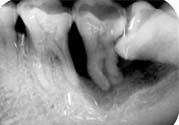

5、如果智齒經(jīng)常疼,而且疼的比較厲害,可能已經(jīng)引發(fā)牙冠周軟組織發(fā)炎,所以導(dǎo)致智齒腫脹、疼痛;再如果智齒長(zhǎng)的位置很歪,影響其它牙齒正常咀嚼,也影響美觀,最好是考慮拔牙。拔牙前提是確保牙冠周圍沒(méi)有炎癥,才能安排拔牙,免除后顧之憂,拔智齒是拔牙里最難的一種,所以一定要到正規(guī)口腔醫(yī)院,請(qǐng)正規(guī)醫(yī)師進(jìn)行專業(yè)拔牙。

1、冠周炎:智齒因阻生而使牙冠不能完全外露,牙冠周圍的牙齦成袋狀,極易積存食物、滋養(yǎng)細(xì)菌。當(dāng)全身抵抗力下降時(shí)引起急性冠周炎。

3、第二磨牙齲壞:向前傾斜的阻生智齒,因經(jīng)常在鄰牙間積存食物,易發(fā)生鄰牙(下頜第二磨牙)齲壞。